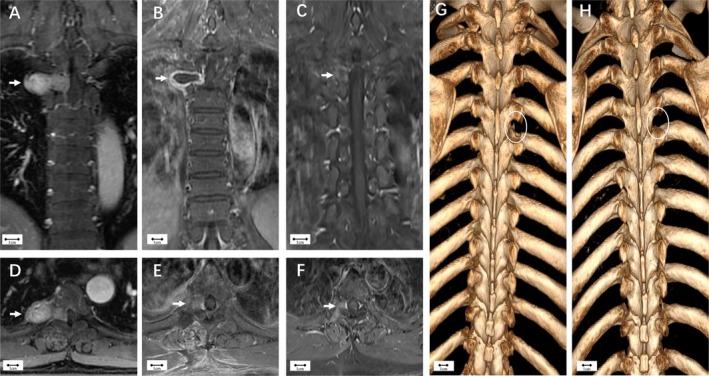

经峡部入路行胸段硬膜外神经鞘瘤囊内切除术:41例病例系列的临床可行性研究

Thoracic spinal canal schwannomas can pose surgical challenges when extending into intra- and extra-foraminal regions and the thoracic cavity. This article aims to elucidate the technical nuances and clinical feasibility of the isthmic approach for treating thoracic extradural schwannomas via intracapsular resection.

当胸段椎管神经鞘瘤延伸至椎间孔内和椎间孔外区域以及胸腔时,手术治疗会面临挑战。本文旨在阐明通过囊内切除治疗胸段硬膜外神经鞘瘤的峡部入路的技术细节和临床可行性。